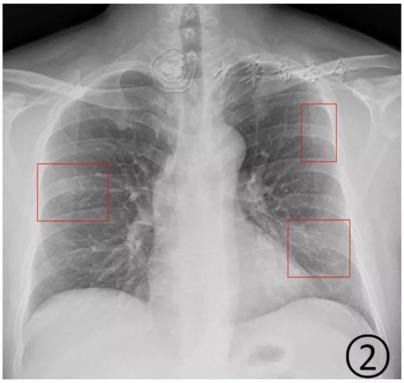

▲白肺(图片来自网络)按照国家卫健委发布的新型冠状病毒肺炎试行第六版诊疗方案之中的临床分型,新冠肺炎分为轻型、普通型、重型及危重型。在患者的肺部CT中,轻型者没有比较明显的肺炎改变;普通型者以肺部出现局限性斑片状或很多节段性片状“病灶”为主(图②);重型者双肺可出现较多的白色小斑片“病灶”,部分融合成大片状“病灶”(图③);危重型者会有“白肺”表现(图④)。

▲从上到下依次为普通型、重型及危重型新冠肺炎患者的肺部CT表现(图片来自网络)